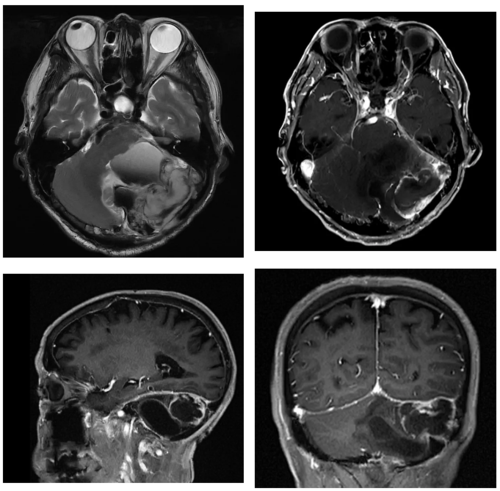

影像学检查(头颅CT及MRI)结果令人担忧,提示左侧小脑半球肿瘤复发,病灶与关键静脉窦(左侧横窦和乙状窦)关系密切,且内部已伴有出血,引发严重颅内高压。更棘手的是,磁共振静脉成像(MRV)显示,患者左侧主要静脉回流通道 — 颈静脉及静脉窦系统疑似被肿瘤侵犯而未显影,且前次手术后导致枕部肌肉萎缩,病变完全破坏前次手术修补的硬脑膜,这极大增加了手术风险与难度,稍有不慎可能导致致命性大出血及术后脑脊液漏从而危及患者生命。

▲术前MRI检查影像